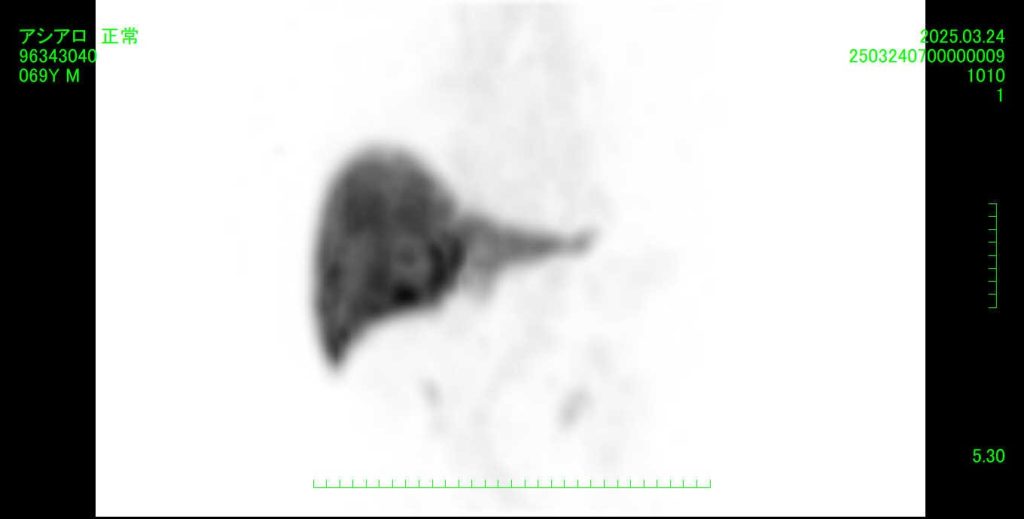

肝アシアロシンチグラフィ

正常な肝細胞に取り込まれる薬剤を使用し、肝障害の程度(肝機能予備能)を調べられる検査です。食事などの摂取により肝血流量が増加するので、当日の食事は検査終了まで控えていただきます。

写真提供:シーメンスヘルスケア株式会社